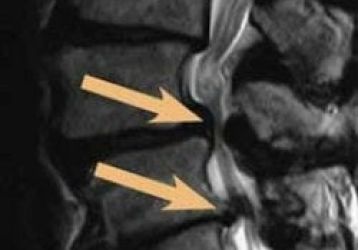

Причины и разновидности дорзальной грыжи диска — диагностика и лечение

Можно ли вылечить дорзальную грыжу диска: разновидности патологии, основные признаки, причины появления, консервативное и оперативное лечение, профилактика.